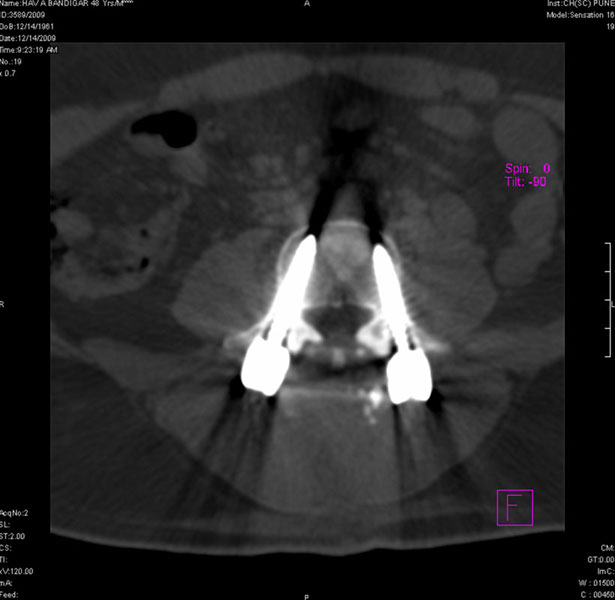

Spondylolisthesis malformations

Spondylolisthesis implies slippage of one lumbar vertebra over the next one, causing pain and nerve compression. Patient can also have difficulty in walking and numbness of the legs. Usually these patients need evaluation lumbar spine by MRI and CT scan, followed by spinal instrumentation and fusion.